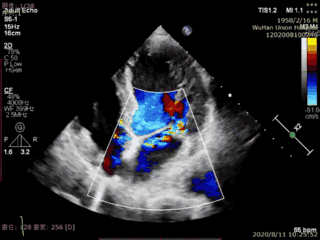

本例患者是一名高龄男性,合并多种疾病,术前超声心动图显示二尖瓣后叶P2脱垂、连枷伴重度二尖瓣反流。手术在食道超声引导下进行,植入1枚IIIs型二尖瓣夹合器,术后即刻显示二尖瓣反流消失,导管操作时间不到20分钟,手术取得圆满成功。

术后超声图